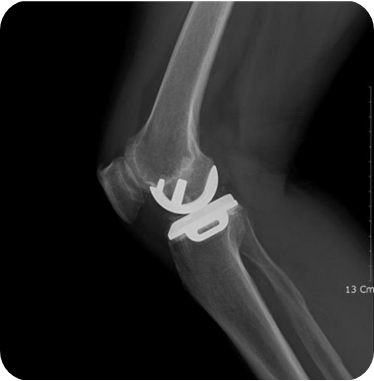

▲ 무릎인공관절 부분치환술 후

• 2) 무릎인공관절 전치환술

무릎의 앞쪽에 10~12cm의 절개를 넣고 무릎 관절 전체를 노출시킨 상태에서 대퇴원위부 및 경골 고평부에 각 뼈의 축에 맞추어 손상된 관절부분을 절제한 후 정해진 기구를 삽입하여 움직임 및 체중부하, 정렬 등에 이상이 없게 만듭니다.

수술 장점

최종 수술방법으로서, 마모된 관절을 정상 무릎관절과 같은 형태의 정렬로 만들기 때문에 회복 후 운동 등이 가능해집니다.

수술 후 관리법

수술 후 다음날부터 어느 정도의 보행과 무릎 관절운동이 가능합니다. 통증 및 회복 정도에 따라 일반적으로 2주간은 입원치료 및 안정가료를 요합니다. 입원기간 중 기계를 이용한 무릎관절각도 회복 운동 및 사두근 강화운동을 권하며, 퇴원 후에도 자가 관절각도 회복 운동 및 사두근 강화운동을 요합니다.